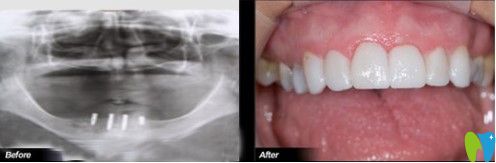

想了解沈陽歡樂仁愛口腔做種植牙的效果如何?我們一起來瞧一瞧何先生做過種植牙之后案列吧!

何先生做過種植牙的案列圖

癥狀描述:何先生,46歲,因?yàn)檠乐軉栴}引起多顆牙松動(dòng),后來導(dǎo)致全口牙脫落。開始,何先生一直佩戴活動(dòng)假牙,但是很影響咀嚼和消化,長期如此身體健康也受到了影響。

歡樂口腔醫(yī)生診斷:上下牙列缺失,全口牙齒只剩下上牙中一顆虎牙。

歡樂口腔治療方案:根據(jù)顧客的口腔內(nèi)部需求,決定植入4顆種植體,然后做覆蓋義齒修復(fù)。